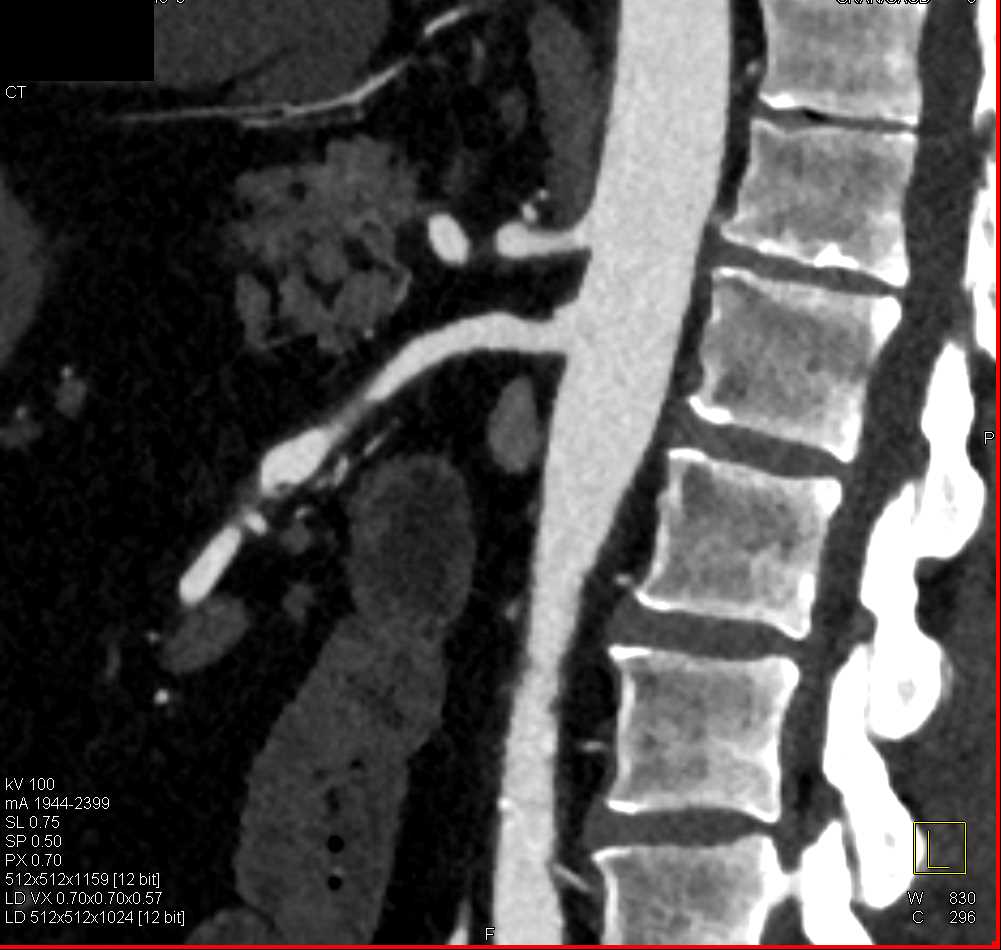

SMA Stenosis